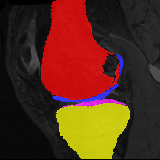

Image

Manual Seg

DA-1

Mono-21

DA-21

Mono-65

Knee MRI experiment: We test our method on 3D knee MRIs from the Osteoarthritis Initiative (OAI) 111https://nda.nih.gov/oai/ and corresponding segmentations of femur and tibia as well as femoral and tibial cartilage [1]. From a total of 507 labeled images, we use 200 for training, 53 for validation, and 254 for testing. To test registration performance we use 10,000 random image pairs from the test set. All images are affinely registered to an atlas built from the training images, resampled to isotropic spacing of 1mm, cropped to and intensity normalized to [0,1]. In addition, right knee images are flipped to be consistent with left knees. For training, the loss weights are , , and based on approximate hyper-parameter tuning. Note that when computing from the displacements, the image coordinates are scaled to [-1, 1] for each dimension following the convention in the interpolation function of PyTorch.

Results: All trained networks are evaluated using Dice overlap scores between predictions and the manual segmentations for the segmentation network, or between the warped moving segmentations and the target segmentations for the registration network. Tabs. 1 and 2 show results for the knee and brain MRI experiments respectively in Dice scores (%). Fig. 2 shows examples of knee MRI registrations and brain MRI segmentations.

Qualitative results: DA achieves more anatomically consistent registrations than the mono-networks on the knee (Fig. 2) and Brain MRI samples (see supplementary material).